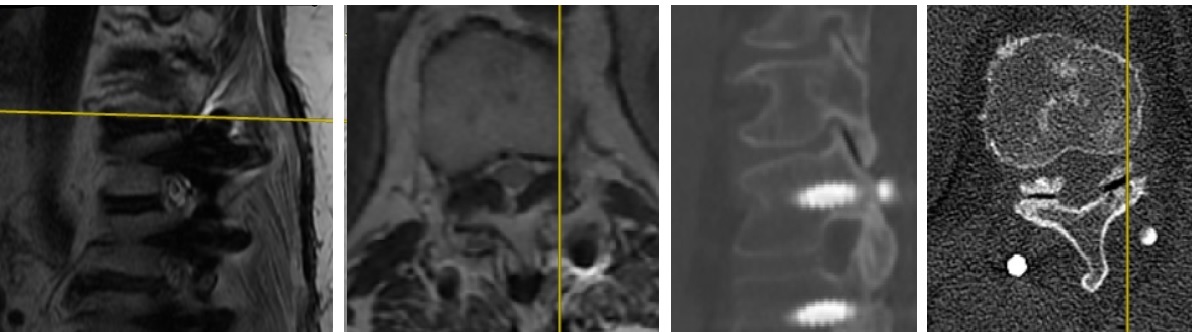

Postop AP Radyolojik Görüntü Postop Lateral Radyolojik Görüntü

Resim 7: Ameliyat sonrası (postop) direkt grafiler. PEEK rod ile dinamik stabilizasyon uygulanmıştır.

Ameliyatta eski ensizyon açılarak titanyum rodlar çıkartıldı. L4-5 seviyesi açılarak kanal içi ve foramen çıkışları dekomprese edildi. Disk içi boşaltılarak otojen kemik greft ile dolduruldu. Gevşemiş L4 ve L5 vidaları çıkartıldı. L4 vidaları kalın vidalarla değiştirildi, L5 seviyesine vida konmadı. S1 ve S2 seviyelerine vida kondu (S1 medial ve kaudal yönelimli, S2 vidaları laterale ve kraniuma yönelimli). L2 vidalarından S2 vidalarına uzanan birer PEEK rod ile sistem stabilize edildi.